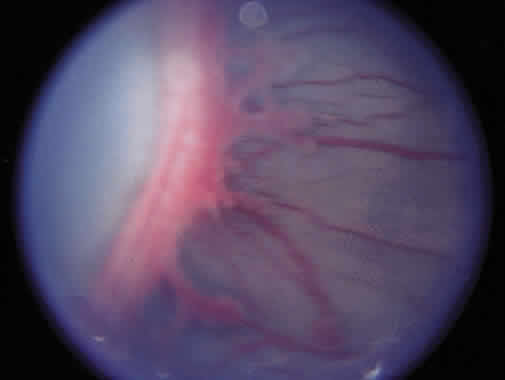

To define location, the retina was divided into three zones with the optic nerve as the center, since retinal vascular growth proceeds from the disc toward the ora serrata (Fig. 2). Zone I consists of a circle, the radius of which extends from the disc to twice the distance from the disc to the center of the macula (twice the disc-fovea distance in all directions from the optic disc). Zone II extends from the edge of zone I peripherally to a point tangential to the nasal ora serrata and around to an area near the temporal anatomic equator. Zone III is the residual temporal crescent of retina anterior to zone II. This is the zone that is vascularized last in the premature eye, and it is the zone most frequently involved with ROP. The extent of disease is specified as hours of the clock (see Fig. 2). The second parameter specified in the 1984 classification is staging of the disease, that is, the degree of abnormal vascular response observed. Four stages were recognized, and staging for the eye as a whole receives the stage of the most severe manifestation of ROP present. Stage 1 (demarcation line) is defined as a thin but definite structure that separates avascular retina anteriorly from the vascularized retina posteriorly. Abnormal branching or arcading vessels are seen leading up to the line. It is flat and white and is in the plane of the retina. Stage 2 (ridge) is present when the line of stage 1 has grown, has height and width, and occupies a volume extending up out of the plane of the retina. The ridge may be pink or white, and vessels may leave the plane of the retina to enter it. Small tufts of new vessels may be seen on the surface of the retina posterior to the ridge. These vessels do not constitute fibrovascular growth, which is a necessary condition for stage 3 ROP. Stage 3 (ridge with extraretinal fibrovascular proliferation) exists when extraretinal fibrovascular proliferation is added to the ridge of stage 2 ROP (Fig. 3). Stage 3 is arbitrarily further subdivided into mild, moderate, and severe. Stage 4 (retinal detachment) is the addition of retinal detachment to stage 3 findings. Traction or exudation cause the retinal detachment.

Fig. 3. Stage 3 retinopathy of prematurity.